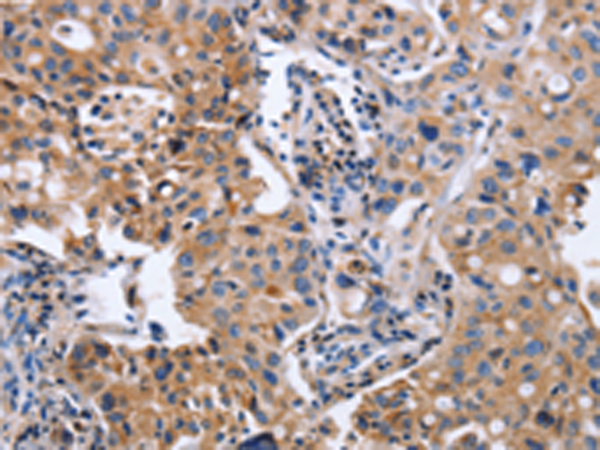

分类: 科研抗体货号: P07404别名: UKLF应用: IHC反应种属: Human